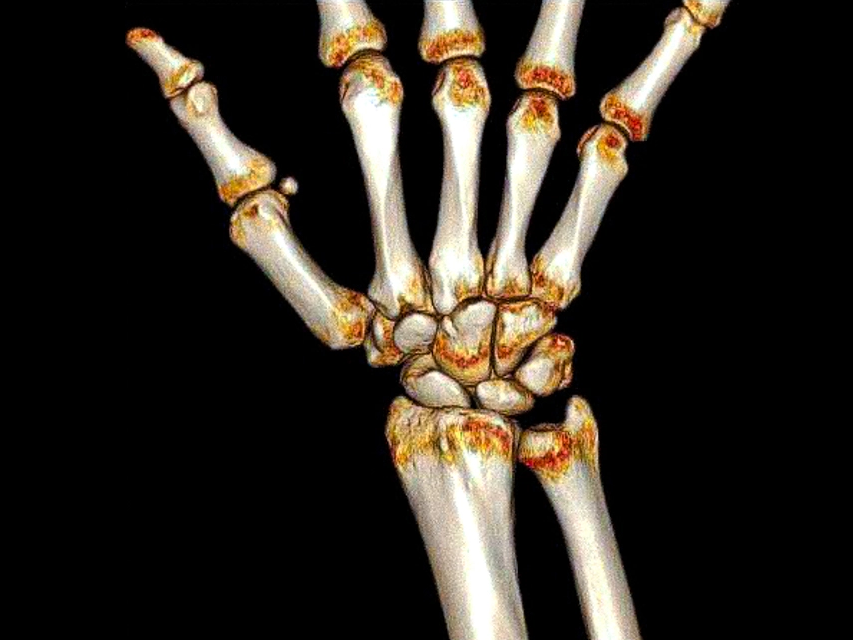

После прохождения процедуры КТ лучезапястного сустава по адресу любой выбранный вами клиники, вы получаете заключение от врача на листе А4 и несколько снимков с трехмерным изображением своего запястья. С этим заключением и снимками весьма желательно посетить своего лечащего врача по месту жительства для получения от него рекомендаций по дальнейшему лечению. Эти рекомендации могут носить медикаментозный или иной характер, но они всегда подобраны индивидуально.